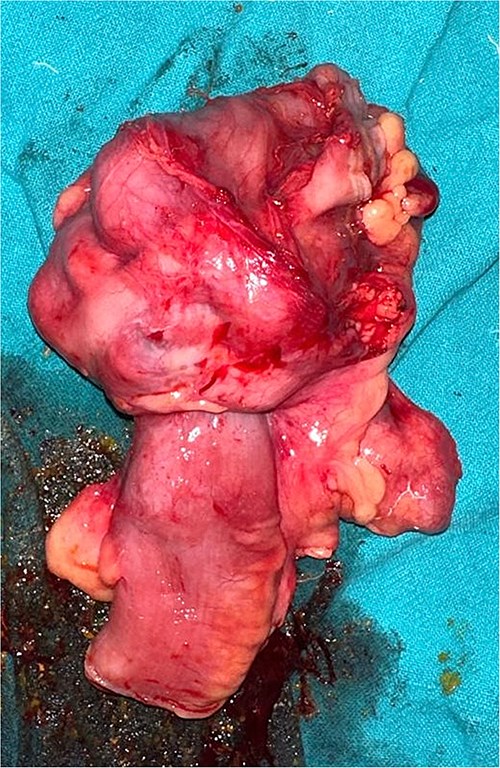

The patient was planned for elective surgery and underwent midline laparotomy. Upon exploration, a long 6 cm segment of ileocolic intussusception was identified along the evidence of chronic inflammation. Because of suspicion of malignancy, manual reduction of intussusception was not done. Multiple enlarged mesenteric lymph nodes were seen. The entire abdominal cavity and all the solid organs diligently inspected to rule out any evidence of metastasis. A right hemicolectomy with mechanical end to end ileo-transverse anastomosis was performed and specimen sent for histopathological examination (Fig. 3).

Section of resected specimen showing telescoping of distal ileum into cecum due to a lobulated mass.

On gross examination, growth seen involving ileocecal junction extending upto caecum measuring 6.5 × 6.0 × 4.3 cm. Cut section showed solid creams white firm to friable areas with mucoid consistency at places. A nodular growth is identified in the attached mesentery measuring 3.5 × 2 × 2 cm. On cut section solid white areas are seen along with focal area showing mucoid consistency. The histopathological report concluded mucinous adenocarcinoma of caecum, pT3N1MX, with evidence of lymphovascular invasion. The tumor invaded through the muscular propria layer (Figs 4 and 5). Additionally, acute appendicitis was found.